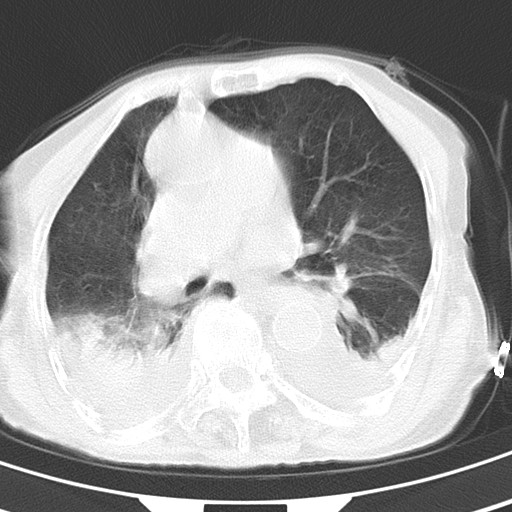

标题: CT21467:女,93岁,摔伤后检查。

女,93岁,摔伤后检查。

右侧锁骨\\肩胛骨骨折、右侧湿肺,心功能不全伴双侧胸腔积液,右下肺膨胀不全,左膈破裂或食管裂孔疝,冠脉钙化,心包少量积液,请上传骨窗.

右肺炎症,心功能不全伴双侧胸腔积液,右下肺膨胀不全,食管裂孔疝,冠脉钙化,心包少量积液,左侧肋骨骨折,右肩甲骨粉碎性骨折。93岁,高寿哇!

右肺炎症,心功能不全伴双侧胸腔积液,右下肺膨胀不全,食管裂孔疝,冠脉钙化,心包少量积液,左侧肋骨骨折,右肩甲骨粉碎性骨折。